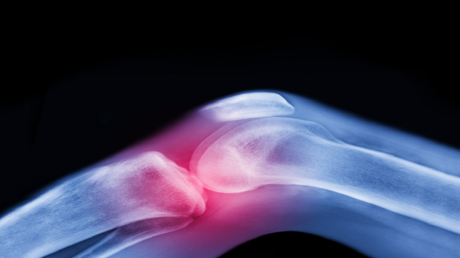

العلاج الأقوى لآلام المفاصل قبل اللجوء إلى الأدوية والجراحة

تعتبر آلام المفاصل وتيبّس الركبتين وأوجاع الوركين من الشكاوى الشائعة بين كبار السن، وغالبا ما يُقبل بها كجزء طبيعي من أعراض الشيخوخة.